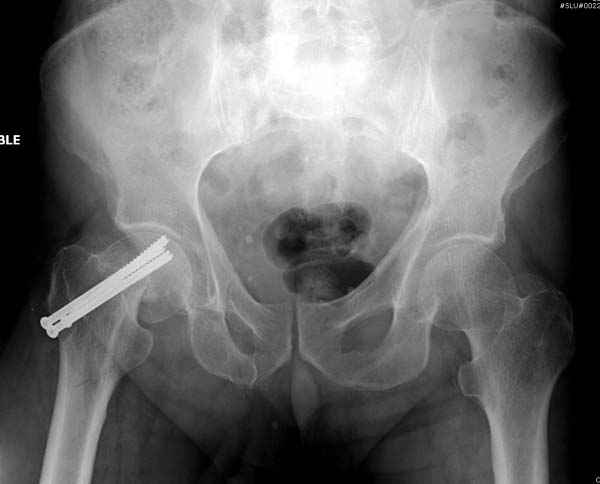

Профилактику дальнейшего раскола неполного перелома шейки провели тремя канюлированными шурупами.

На второй день после выписки упал дома. Снимки приложены. Коллеги рекомендуют удаление шурупа и вытяжение. Что делать?